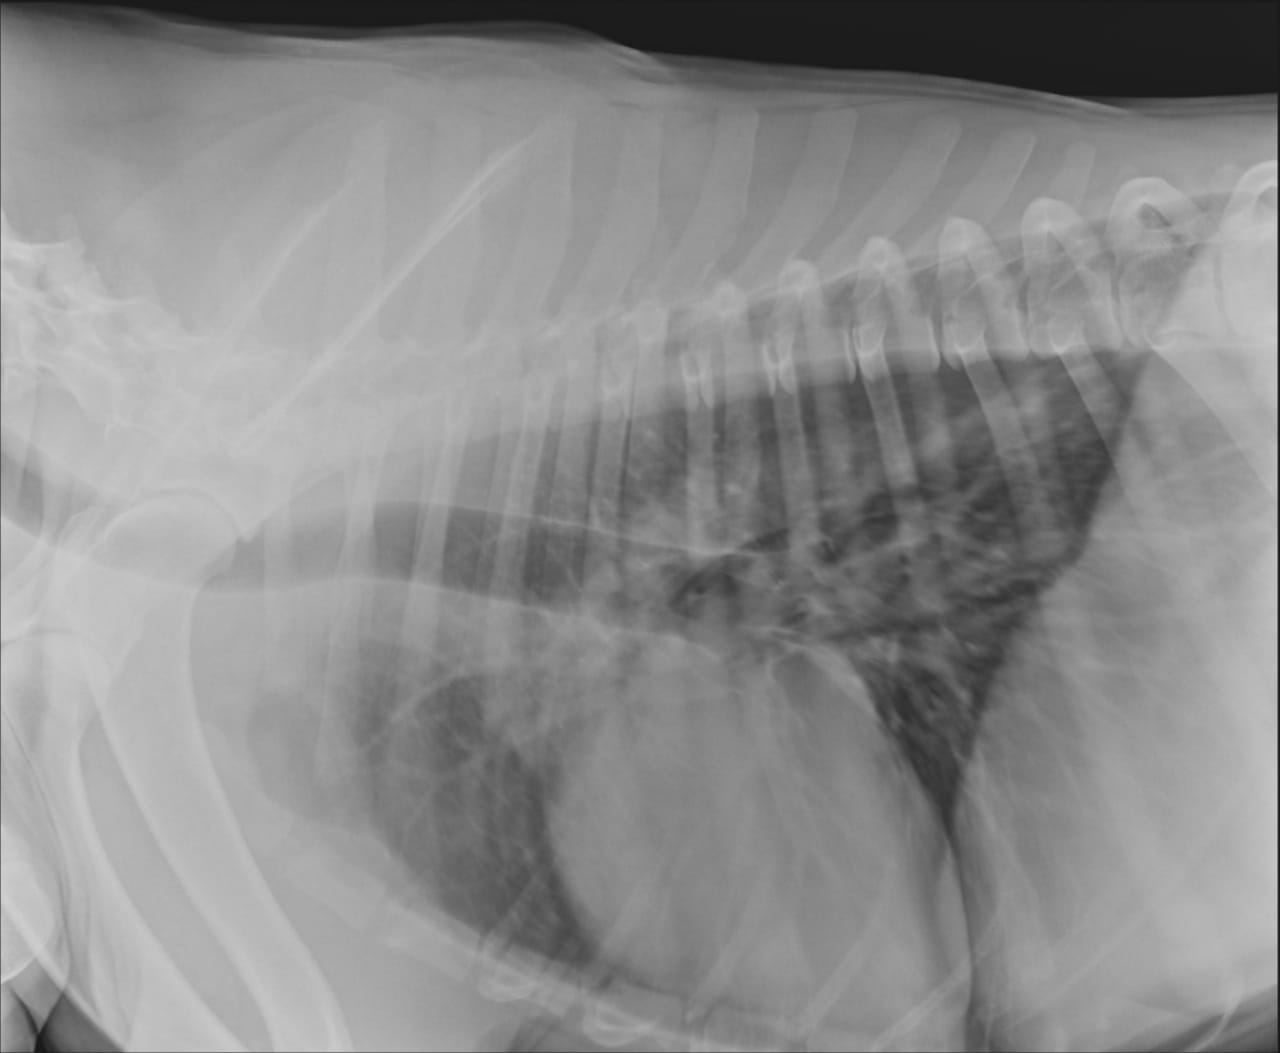

Анализы Арчи. Сердца и легких

Вложения

IMG-20220719-WA0100.jpg

IMG-20220719-WA0102.jpg

IMG-20220719-WA0104.jpg

IMG-20220719-WA0103.jpg

IMG-20220719-WA0105.jpg